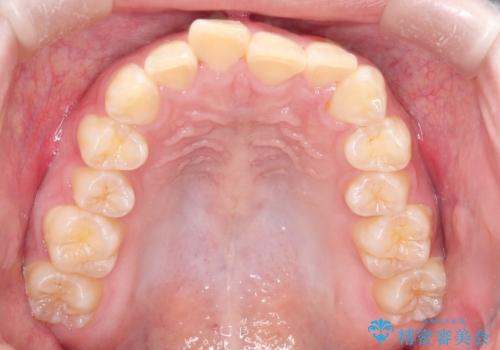

インビザラインで前歯のガタガタをきれいな歯並びへ

- 前歯のガタガタが気になるとのことで来院されました。

上顎の前歯の叢生があったのと、下あごの前歯が通常より1本欠損(先天欠損)していました。

上顎の歯と歯の間をわずかに削りスペースをつくり、並べる計画としました。インビザライン治療を選択されました。